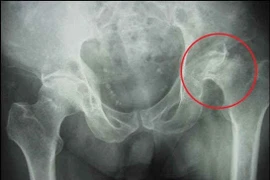

(khoahocdoisong.vn) - Hoại tử vô khuẩn chỏm xương đùi hay còn gọi là hoại tử vô mạch (Avascular Necrosis) chỏm xương đùi là bệnh có tổn thương hoại tử tế bào xương và tủy xương do thiếu máu nuôi trên chỏm xương đùi.